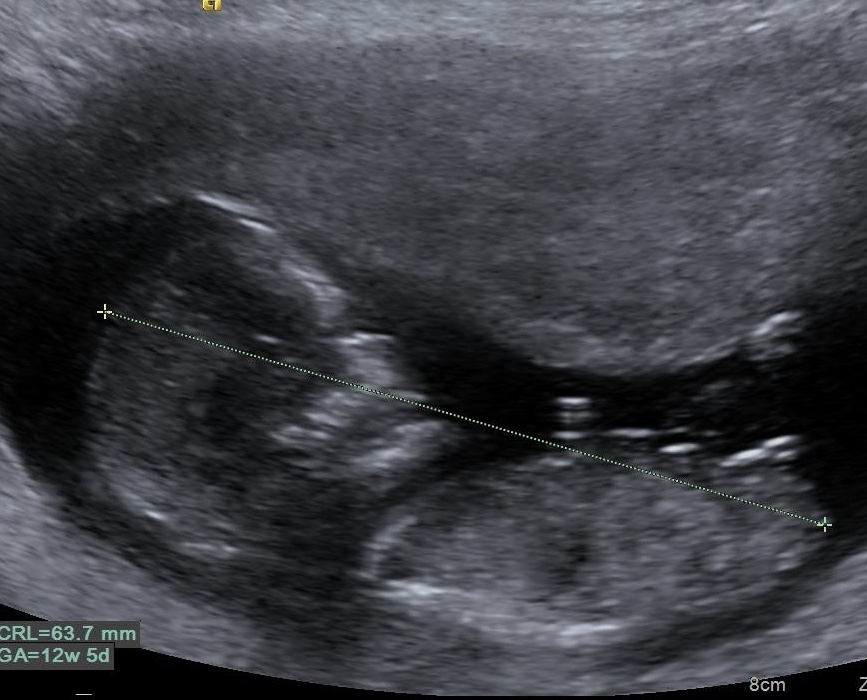

Opinions? 12 weeks 5 days :)

Baby was very squirmy so this is as good as I could get lol